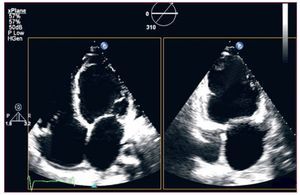

La utilización de los ecógrafos de bolsillo se ha debatido ampliamente. La Sociedad Europea de Ecocardiografía considera que estos aparatos facilitan una extensión del examen clínico, y así se debe valorarlos1; los resultados obtenidos tienen claras limitaciones y no reemplazan un ecocardiograma convencional; es recomendable también que los usuarios tengan formación acreditada para esta. Las sociedades americanas de imagen cardiaca han manifestado opiniones similares, de manera que en la definición de ecocardiógrafo no incluyen estos dispositivos2, que se consideran estetoscopios ultrasónicos de bolsillo. Se ha publicado una guía3 de «usos adecuados de la ecocardiografía» que facilita el análisis de las indicaciones. En ecocardiografía transesofágica (ETE)4, el 21% de las indicaciones son inapropiadas; no obstante, los autores refuerzan una opinión muy difundida: independientemente de la indicación, se obtienen datos no hallados en el ecograma transtorácico en casi la mitad de los estudios, especialmente en la búsqueda de fuente embólica. Existe la convicción de que el número total de estudios transtorácicos no se rige por estas guías5, en buena parte, porque existe un porcentaje creciente (10%) de indicaciones no reflejadas en ellas. Se ha difundido la ecocardiografía transtorácica multiplanar mediante adquisición omniplanar rotatoria, que permite obtener múltiples planos sin mover el transductor, lo cual es especialmente útil en pacientes con espacios intercostales pequeños y en la ventana apical para obtener tomografías apicales de dos o tres cámaras adecuadas; con este tipo de transductores matrix array puede reducirse el tiempo de exploración6 (fig. 1).

Figura 1. Ecografía tridimensional en tiempo real. Adquisición rotatoria multiplanar: sobre una imagen apical convencional, obtenemos un apical de dos cámaras donde observamos trombo apical en un ventrículo isquémico (flecha).